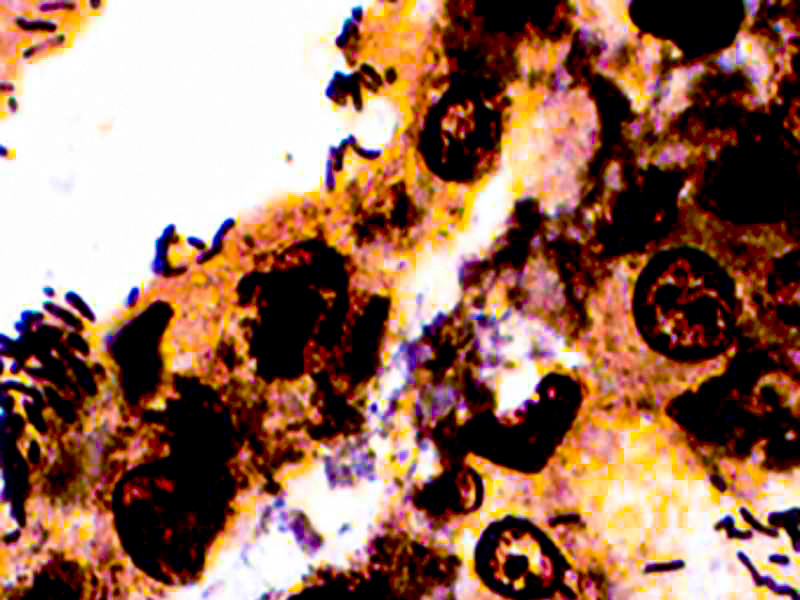

The Warthin-Starry Stain Kit is intended for use in the visualization of Spirochetes, Helicobacter pylori, Legionella pneumophila, and Cat Scratch Fever bacteria. This kit may be used on formalin-fixed, paraffin-embedded sections.